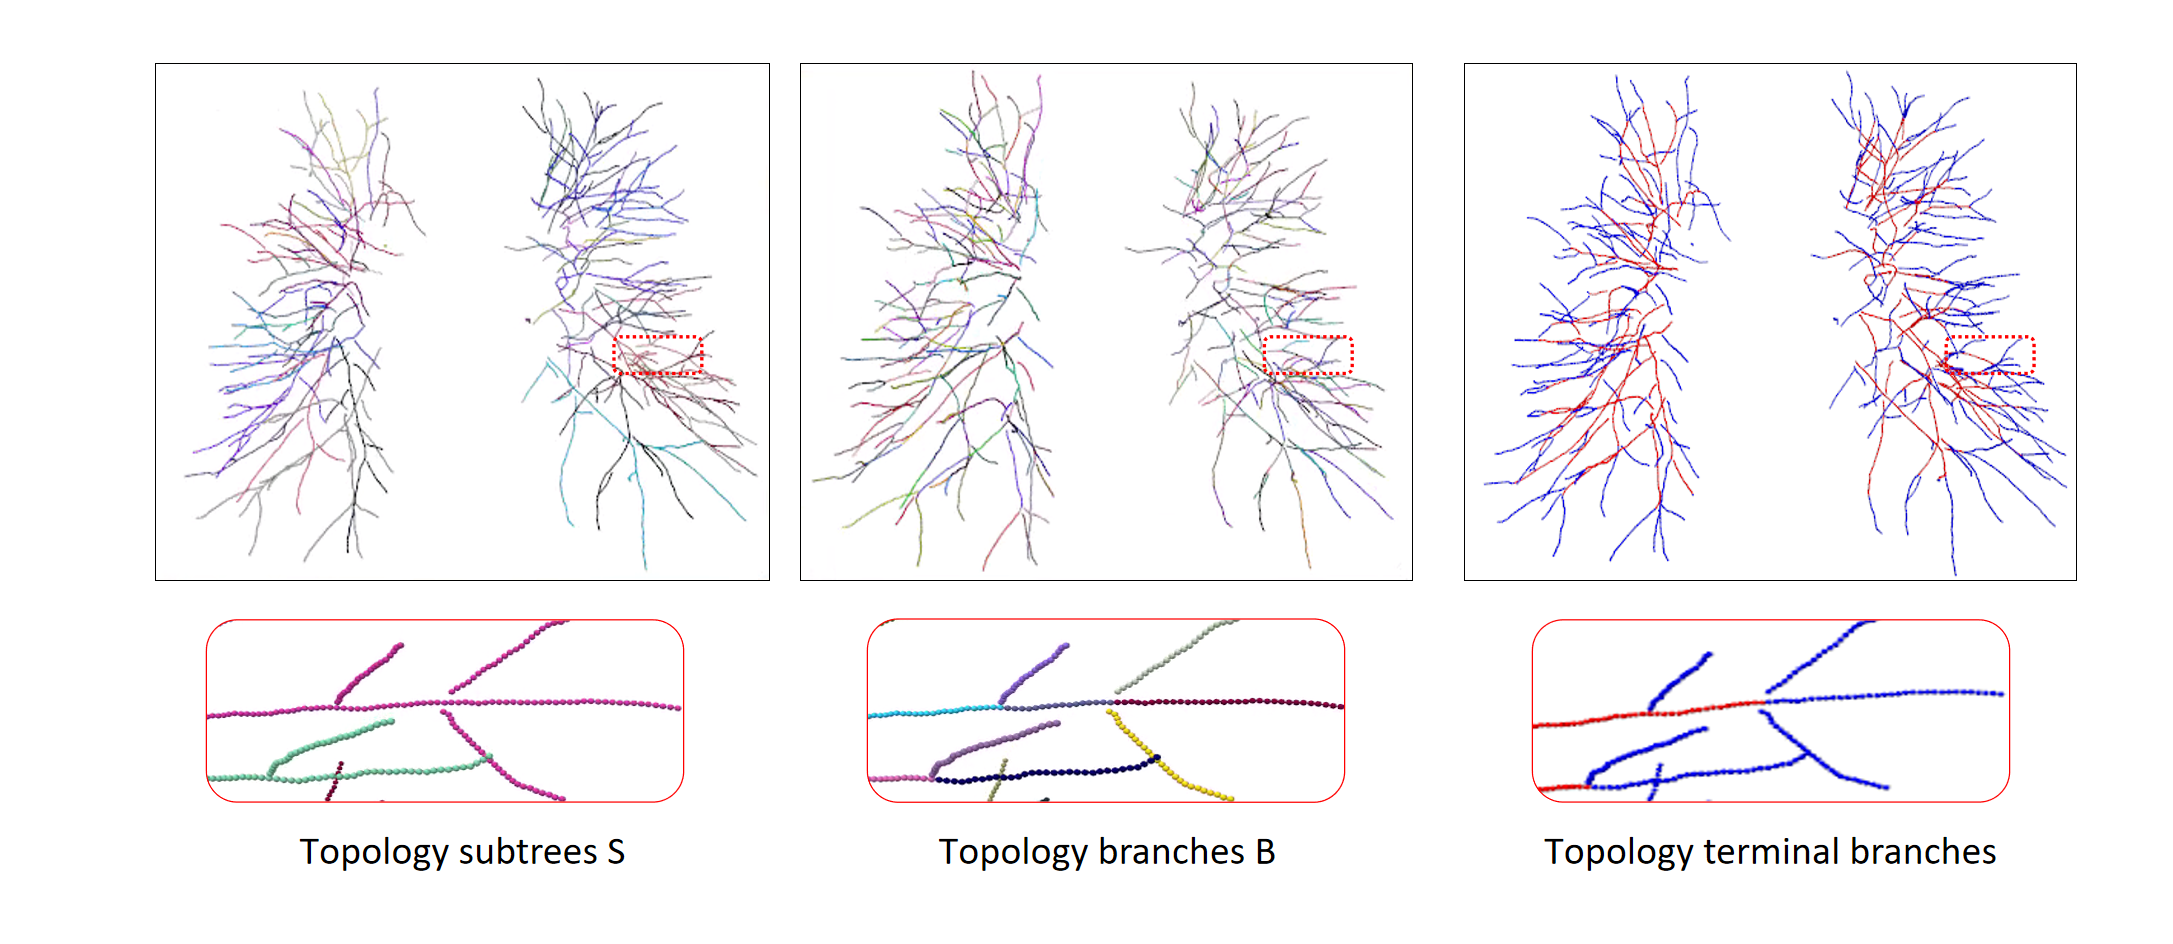

2.3 Optimizer and A/V Result

In order to separate arteries and veins, topological subtrees and topological branches are extracted from topological tree T, and topological subtrees S are roughly extracted from root nodes through uniform distribution of arteries and veins, and subtrees are refined according to tubular features and scale information. The subtree root node in G is extracted, and then traverse each subtree root node down to the terminal points to obtain the corresponding subtree. However, due to the presence of arterial and venous interlacing, it is possible that arterial subtrees contain venous branches, which is inevitable. The topological branch B is extracted from the backtracking path of the end points, where the bifurcation points and terminal points are considered to be the end points to ensure that each branch is either an artery or a vein. The results of a topology subtree and topology branch are shown in Fig. 9.

Finally, the topology optimizer extracts the topology subtree and topology branch refinement results by the method in Section 2.3. The results of a topology subtree and topology branch are shown in Fig. 9. Then, we use topology subtrees and topology branches for postprocessing. As shown in Table 3, the proposed topology optimizer is superior to the subtree-based and branch-based topology optimization in accuracy. Fig. 14 and 15 show the reconstructed results of different topology strategy optimizers. The results in Fig. 14 show that when the number of points on the branch is small, and the branch-based topology optimization method is prone to predict errors. This finding is mainly because the branch-based refinement strategy focuses on the relationships within the branches and ignores the topological relationships between branches. As shown in Fig. 15, topology optimization based on subtree strategy is prone to prediction errors in the case of arterial-vein intersection. This finding is mainly because the arterial/venous intersection point in the extraction process of topological subtree is easily mistaken for the bifurcation point of arterial subtrees due to the complex structure of the vascular tree, arteries and veins interweave, and finally the venous branches are classified as arterial subtrees, resulting in the classification error.